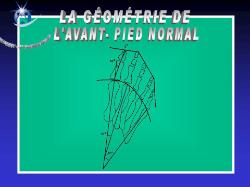

Architecture d’un avant pied normal

La phalange du gros orteil et le premier métatarsien sont pratiquement dans le même alignement.

Le but des techniques chirurgicales traitant l’hallux valgus est de rétablir l’équilibre de l’avant-pied en ramenant le premier métatarsien vers le second et en réalignant le métatarsien et la phalange du gros orteil. Ces traitements ne se contentent pas de « raboter » la bosse (exostose) mais s’attaquent à la cause de la déformation en réduisant l’angle entre le métatarsien et la phalange.